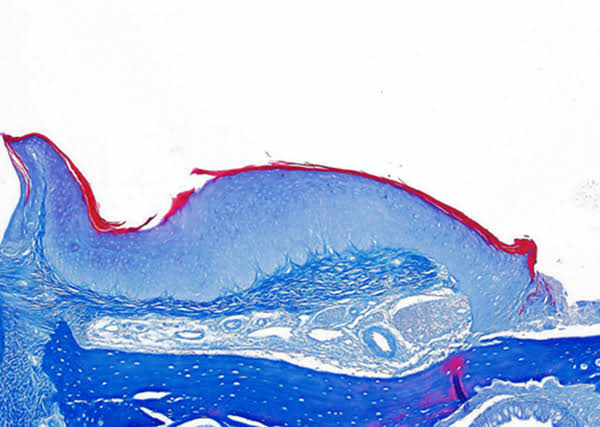

為促進科學(xué)文化發(fā)展,活躍專委會的科技人文氛圍,培養(yǎng)科研工作者的創(chuàng)新意識,激發(fā)他們發(fā)現(xiàn)美、創(chuàng)造美的熱情和興趣,本次年會特別增加了一項“生命的藝術(shù)——首屆年度顯微圖片展”活動。在專委會發(fā)出征稿通知之后,來自全國近20 所院校的師生積極響應(yīng),共投稿顯微攝影作品125 幅。經(jīng)以王松靈院士為主席的九位審讀專家組成員在線上線下的認真審閱和討論,從圖片的原創(chuàng)性、科學(xué)性和藝術(shù)性三個方面進行綜合考量,最終確定年度圖片1 幅,年度提名圖片20 幅。在此匯集成冊,與各位同仁分享、交流。

這些作品幾乎均為創(chuàng)作者在日??蒲泄ぷ髦幸圆煌募夹g(shù)手段捕捉到的微觀生命瞬間,科學(xué)的“透鏡”似乎為我們展現(xiàn)出一幅幅藝術(shù)的“魔幻”,一邊是細胞、分子層面的微觀抵達,另一邊好似一塊既陌生又熟悉的“優(yōu)詩美地”。這里,本是科學(xué)嚴謹?shù)念I(lǐng)地,因為其關(guān)乎生靈,便開啟人們自由逸放的審美思緒。在此,我們驚嘆中國古代哲學(xué)體系中“天人合一、道法自然”的天道規(guī)律。原來早于現(xiàn)代科學(xué),這種“盡精微而致廣大”的宇宙觀便已根植于我們生存的大地。感謝各位作者以他們現(xiàn)代技術(shù)的視野,為我們定格生命律動的瞬間,張揚蓬勃的藝術(shù)活力。換一個視角,生命的風景便呈現(xiàn)“天地人”的和諧和統(tǒng)一,換一種思路,生命的哲學(xué)便更能詮釋苦難與幸福的非凡境遇。